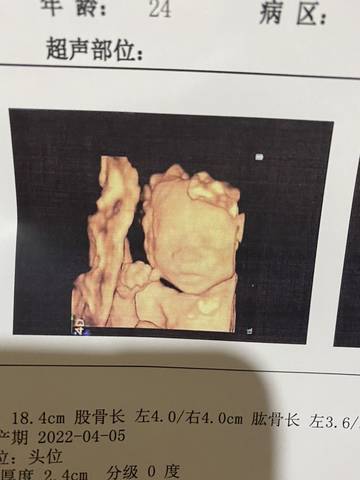

大家快来看看我儿子的四维照,可不可爱

journal_insert_pic_1676859234journal_insert_pic_1676859344